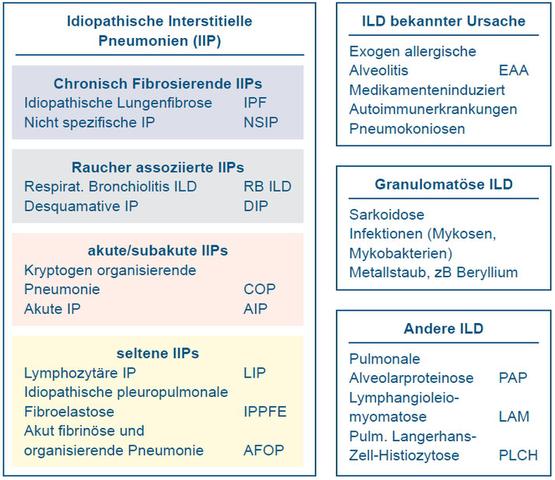

Eine Lungenfibrose entsteht, wenn sich Narben in der Lunge bilden, die oft auf langjährige Entzündungen zurückzuführen sind. Mehrere Erkrankungen und Schadstoffe können eine Lungenfibrose verursachen. Sie entwickelt sich meist über mehrere Jahre mit wenigen Symptomen und führt letztendlich zu chronischem Husten, Atemnot, eingeschränkter Leistungsfähigkeit, schwerem Sauerstoffmangel und Tod.

Die Lungenfibrose entsteht durch die Bildung von Narben in der Lunge, die oft auf langjährige Entzündungen zurückzuführen sind. Verschiedene Erkrankungen und Schadstoffe können eine Lungenfibrose verursachen. Sie entwickelt sich meist über mehrere Jahre ohne viele Symptome und führt letztendlich zu chronischem Husten, Atemnot, eingeschränkter Leistungsfähigkeit, schwerem Sauerstoffmangel und Tod.

Eine Lungenfibrose entsteht, wenn sich Narben in der Lunge bilden, die oft auf langjährige Entzündungen in der Lunge zurückzuführen sind. Es gibt verschiedene Erkrankungen und Schadstoffe, die eine Lungenfibrose verursachen können. Die Krankheit entwickelt sich meist über mehrere Jahre mit wenigen Symptomen und führt letztendlich zu chronischem Husten, Atemnot, eingeschränkter Leistungsfähigkeit, schwerem Sauerstoffmangel und Tod. Neue medikamentöse Therapiemöglichkeiten geben jedoch Hoffnung für bestimmte Formen von Lungenfibrose.

Die Lungenfibrose ist eine Erkrankung, bei der sich Narben in der Lunge bilden. Diese Narbenbildung wird oft durch langjährige Entzündungen in der Lunge verursacht. Es gibt verschiedene Ursachen und Risikofaktoren für die Entwicklung einer Lungenfibrose, darunter Schadstoffe und bestimmte Lungenerkrankungen.